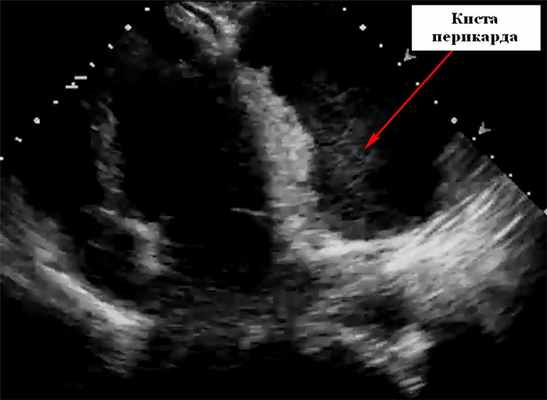

Характерная находка на рентгенограмме грудной клетки - округлая, четко очерченная рентгеноконтрастное образование под правым кардио-диафрагмальным углом, прилегающая к диафрагме. Сообщалось о других местах, таких как левый сердечно-диафрагмальный угол или где-либо еще в верхнем средостении. На эхокардиографии они выглядят как локализованное свободное от эхонегативное пространство, прилегающее к границе сердца, чаще всего около правого предсердия. Они могут исказить нормальную форму предсердия. При эхокардиографии киста выявляется как округлая эхонегативная кистозная структура, прилегающая к правому предсердию или желудочку, которая не сообщается с перикардиальным пространством. Чреспищеводная эхокардиография может дать лучшее определение ее размерам. Большие кисты перикарда могут привести к сдавлению правой камеры сердца и появлению симптомов. Цветное допплеровское картирование и импульсный допплеровский спектр при настройках на низкой скорости можно использовать, чтобы гарантировать отсутствие фазового потока внутри образования.

На УЗИ кисты перикарда необходимо дифференцировать от локализованного выпота в перикарде, увеличения камеры сердца, диафрагмальной грыжи и злокачественных опухолей. Двумерная эхокардиография может легко отличить анэхогенное содержимое перикардиальной кисты от солидных структур. Типичное расположение кист перикарда в правом сердечно-диафрагмальном угле является еще одним ключом к разгадке, хотя они также могут быть обнаружены в левом сердечно-диафрагмальном углу, воротах и верхнем средостении.

Магнитно-резонансная томография сердца (КМРТ) или компьютерная томография (КТ) обычно используются для подтверждения диагноза, выяснения других анатомических деталей и отличия от новообразований и аневризм. На картинке ниже представлена гигантская киста перикарда на эхокардиографии.

В марте 2012 г. выполнена селективная ангиография коронарных артерий, по результатам которой гемодинамически значимых сужений коронарных артерий выявлено не было. По результатам иммунологического исследования данных, свидетельствующих о миокардите, не получено. По данным эхокардиографии выявлена инкапсулированная полость (киста перикарда?), деформирующая правое предсердие, правый желудочек, размерами 3,5×6 см. Левый желудочек: толщина межжелудочковой перегородки (диаст.) – 1,1 см, толщина задней стенки левого желудочка (диаст.) – 0,8 см, конечный систолический размер – 3,5 см, конечный диастолический размер – 5,3 см, конечный диастолический объем – 133 мл, конечный систолический объем – 51 мл, ударный объем – 82 мл, фракция выброса (по Тейхольцу) – 62%. Левое предсердие: диаметр – 3,5 см. Митральный клапан: не изменен, движение створок разнонаправленное, диаметр фиброзного кольца – 2,7 см. Аортальный клапан: не изменен, диметр фиброзного кольца – 2,4 см. Аорта: диаметр на уровне синуса Вальсальвы – 3,7 см; диаметр восходящего отдела – 3,8 см. Трикуспидальный клапан: не изменен, диаметр фиброзного кольца – 3,5 см.